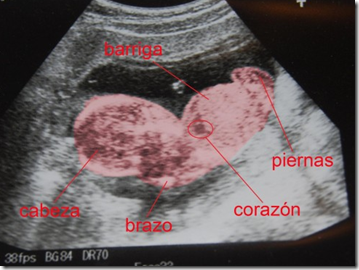

Esas ondas de ultrasonido “chocan” con el tejido corporal y producen un eco que es captado por el ecógrafo. Esa información es traducida en imágenes sobre una pantalla, logrando diferenciar los distintos tejidos o fluidos, como por ejemplo la placenta, el líquido amniótico, el tejido muscular y el tejido óseo. La ecografía nos muestra también los movimientos del bebé en tiempo real, e incluso podremos ver y escuchar el latido de su corazón.

El primer ultrasonido será indicado por su obstetra para controlar la implantación del embrión y su estado de salud. Generalmente la primera ecografía se realiza entre la semana 6 y la semana 12 del embarazo. Al menos se realizarán dos estudios de control más: uno para verificar el estado de los órganos y conocer el sexo del bebé (semana 16 a 20) y otro en alrededor de la semana 32 para controlar el crecimiento del feto.